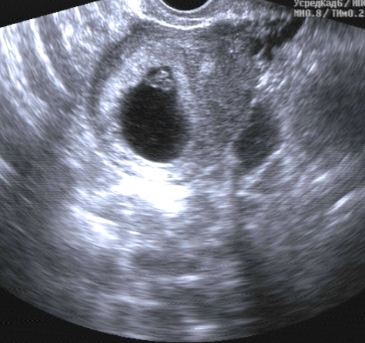

Повторное УЗИ

Прошлый раз ПЯ было всего лишь 3 мм, а сейчас - 25! А внутри - эмбриончик 9,5 мм длиной. 😍 А самое главное - мне врач показал мааааленькую пульсирующую точечку, сердечко моей крохи. И дал послушать, ЧС 135 ударов в минуту.🤗

На прошлом УЗИ, почти три недели назад, у меня была жидкость в околоматочном пространстве, еще какой-то там след от кисты, а сейчас - все чисто. Утверждает, что все хорошо и оно просто рассосалось. Матка в размерах тоже чуть увеличилась уже.